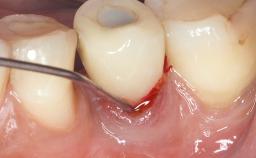

Peri-Implant Mucositis Associated with Misfit of a Cemented Restoration

A 37-year-old male patient was referred to the Department of Periodontology at the University of Bern, Switzerland, by a private dentist. Tooth 21 had been lost due to trauma and had been replaced with an implant and a cemented single crown. The tapered-effect tissue-level implant had a diameter of 4.1 mm, a length of 12 mm, and a sandblasted and acid-etched (SLA) surface (Straumann Dental lmplant System; Institut Straumann AG, Basel, Switzerland). The metal-ceramic crown had been cemented permanently, leaving a submucosal gap between the implant shoulder and the crown margin. Absence of marginal bone loss apical to the polished transmucosal neck of the implant could be observed .